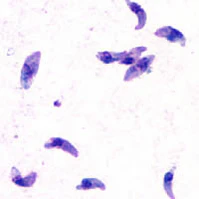

- ксенодиагностика — введение исследуемой пробы мышам. После введения инокулята (суспензии живых клеток для получения новой культуры микроорганизма) мышам в их перитонеальном экссудате обнаруживаются тахизоиты спустя 1 — 2 недели, а в их мозге — цистозоиты (брадизоиты) спустя 2 месяца.